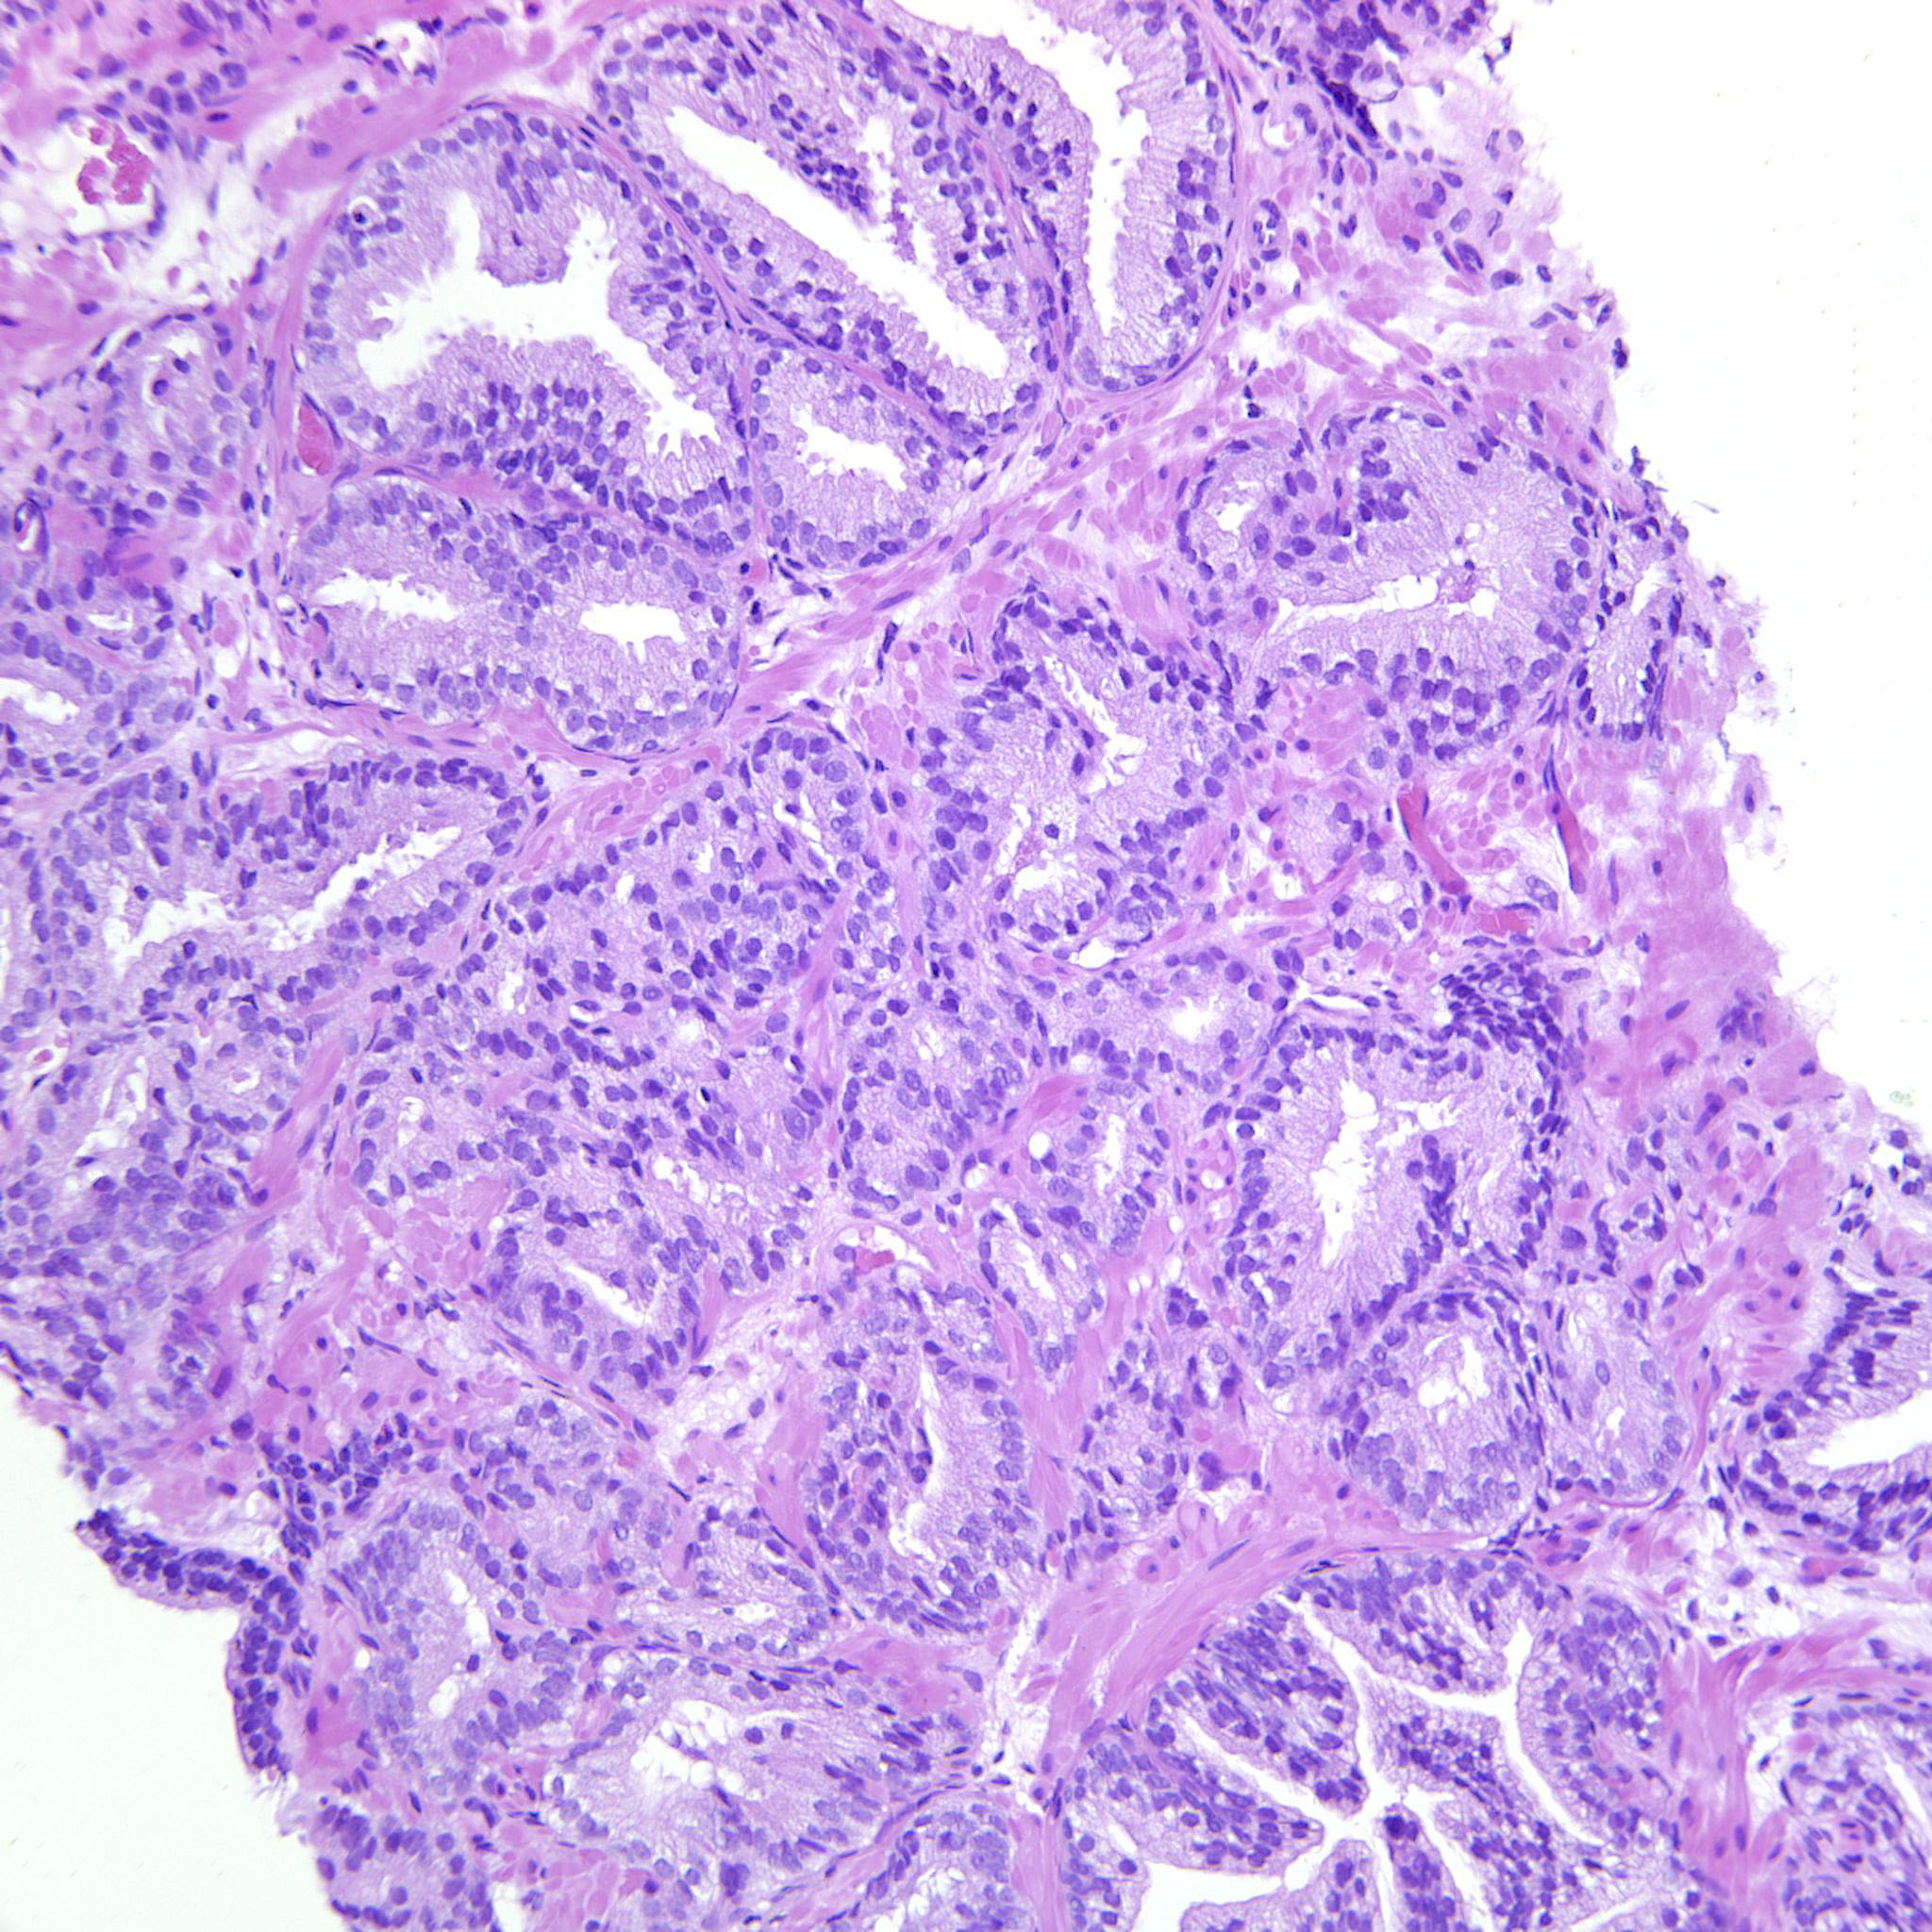

Prostate cancer grading

Case ID: 738